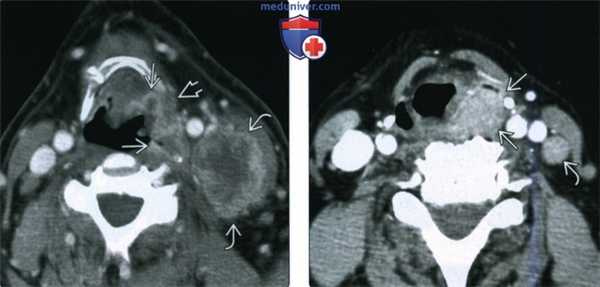

(Слева) При аксиальной КТ с КУ, выполненной мужчине, похудевшему на 18 килограммов, визуализируется объемное образование (ПКР) неправильной формы, минимально накапливающее контраст, возникшее в грушевидном синусе и распространяющееся на наружную стенку ротоглотки, в т.ч. в мягкие ткани за ее пределами. Визуализируются увеличенные вторично измененные лимфатические узлы с признаками экстракапсулярного распространения опухоли в (T4aN3).

(Справа) При аксиальной КТ с КУ у мужчины 82 лет в задненаружной стенке грушевидного синуса визуализируется объемное образование (ПКР). Опухоль (T3N2bM1) сочетается с параличом левой голосовой связки, вызывает метастатическую лимфаденопатию, и метастазирует в легкие.